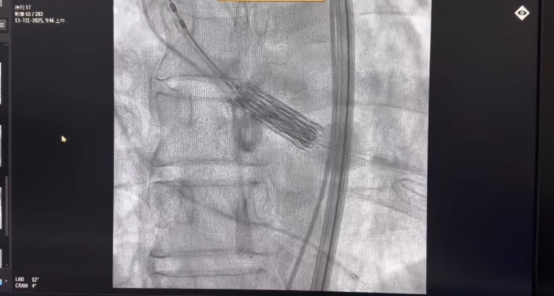

2025年7月13日,我院郭應(yīng)強(qiáng)教授為一名主動(dòng)脈瓣重度狹窄伴反流患者成功實(shí)施機(jī)器人輔助球擴(kuò)式TAVR(Transcatheter Aortic Valve Replacement,經(jīng)導(dǎo)管主動(dòng)脈瓣置換)手術(shù)。術(shù)后患者即刻蘇醒、恢復(fù)良好。這是郭應(yīng)強(qiáng)教授團(tuán)隊(duì)開展的全國首例介入機(jī)器人+TAVR(S3)的臨床試驗(yàn),有望為心臟瓣膜病患者帶來新的手術(shù)方式選擇。該機(jī)器人系統(tǒng)由郭應(yīng)強(qiáng)教授和上海術(shù)濟(jì)客醫(yī)療科技有限公司共同研發(fā),這也標(biāo)志著我院在心臟瓣膜疾病領(lǐng)域再次邁出了精準(zhǔn)化、智慧化的重要一步。

該患者為60歲男性,5+月前無明顯誘因出現(xiàn)心悸。完善超聲心動(dòng)圖提示主動(dòng)脈瓣狹窄(重度)伴反流(中度),二尖瓣狹窄(輕度)伴反流(輕-中度)。術(shù)中,郭應(yīng)強(qiáng)教授在與手術(shù)室相鄰的控制室操作控制臺上的按鍵和手柄,遙控機(jī)器人平臺上的瓣膜器械完成手術(shù)操作。

T AVR手術(shù)在機(jī)器人輔助下,旨在通過高精度、可重復(fù)的操作提升手術(shù)安全性和療效,其核心是通過機(jī)器人系統(tǒng)輔助完成導(dǎo)管操作、瓣膜定位及釋放等關(guān)鍵步驟。該系統(tǒng)采用模塊化設(shè)計(jì),支持亞毫米級精準(zhǔn)操作,并配備力傳感反饋機(jī)制,可實(shí)時(shí)感知導(dǎo)管受力情況,優(yōu)化復(fù)雜血管路徑的導(dǎo)航能力。